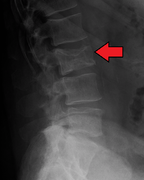

يُشخص المرض مخبريا بعمل عدة فحوصات و تشمل الفحوصات الوظيفية للكلية و قياس كمية الكالسيوم في الدم و عد مكونات الدم. و يستخدم الترحيل الكهربائي للبروتينات للتحري عن بعض البروتينات الغير طبيعية التي يتم إنتاجها بواسطة الخلايا السرطانية. للتحري عن أية كسور في العظام يتم تصوير المريض إشعاعيا بواسطة الجهاز الطبقي أو جهاز الرنين المغناطيسي.

X-ray of the forearm, with lytic lesions.

CT scan of the lower vertebral column in a man with multiple myeloma, showing multiple osteoblastic lesions. These are more radiodense (brighter in this image) than the surrounding cancellous bone, in contrast to osteolytic lesions which are less radiodense.